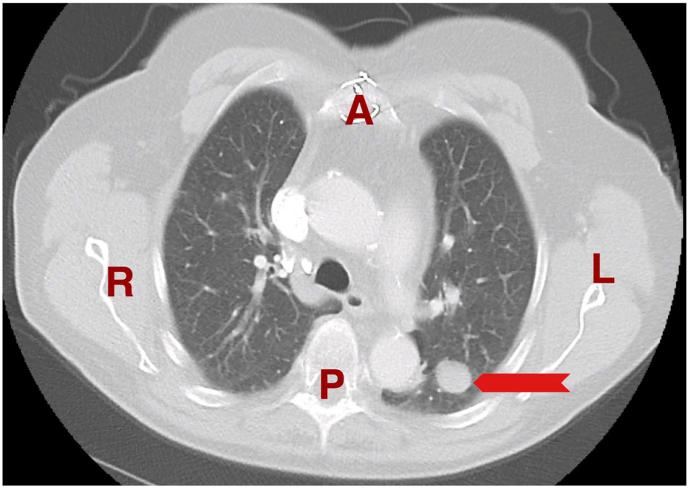

Solitary fibrous tumors of the pleura (SFTPs) are rare neoplasms of mesenchymal origin most commonly arising in the pleura and have a benign biological behavior in the majority of cases. Most patients with SFTPs are asymptomatic; however, symptoms are mostly related to the mass effect within the thoracic cavity. Chest computed tomography (CT) scanning is the radiographic test of choice, but findings lack specificity. Surgical resection is the treatment of choice for most patients. Long-term survival after resection of benign SFTPs is excellent. In this case series, we present two females, one presented with shortness of breath (SOB) and nonproductive cough and the other one was referred because of abnormal x-ray findings. The histological as well as the immunohistochemical examination revealed the mass to be a solitary fibrous tumor of the pleura.

胸膜孤立性纤维瘤(SFTPs)是一种罕见的间叶源性肿瘤,最常起源于胸膜,大多数病例具有良性生物学行为。大多数SFTPs患者无症状;然而,症状大多与胸腔内的肿块效应有关。胸部计算机断层扫描(CT)是首选的影像学检查,但检查结果缺乏特异性。手术切除是大多数患者的首选治疗方法。良性SFTPs切除后的长期生存率很高。在本病例系列中,我们报告了两名女性,一名表现为呼吸急促(SOB)和干咳,另一名因X线检查结果异常而转诊。组织学及免疫组化检查显示该肿块为胸膜孤立性纤维瘤。